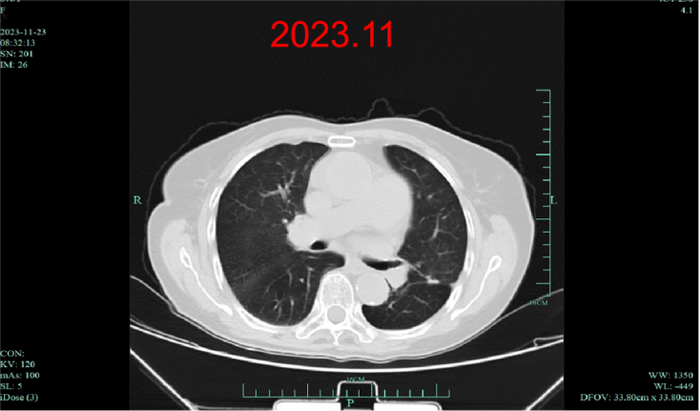

疗效评估:复查时原发灶较基线时明显缩小,达到深度缓解,并在随后治疗中持续缓解长达39个月。

上述病例为初诊转移性NSCLC患者,在基因检测明确BRAF V600E突变后,接受达拉非尼+曲美替尼一线治疗。在服药1月余后复查肺部CT,原发灶较基线时明显缩小,疗效评价达到深度缓解。截至2023年11月最后一次随访,该患者已获得长达39个月的PFS。该病例的治疗过程再次印证了达拉非尼+曲美替尼一线治疗的长生存获益。